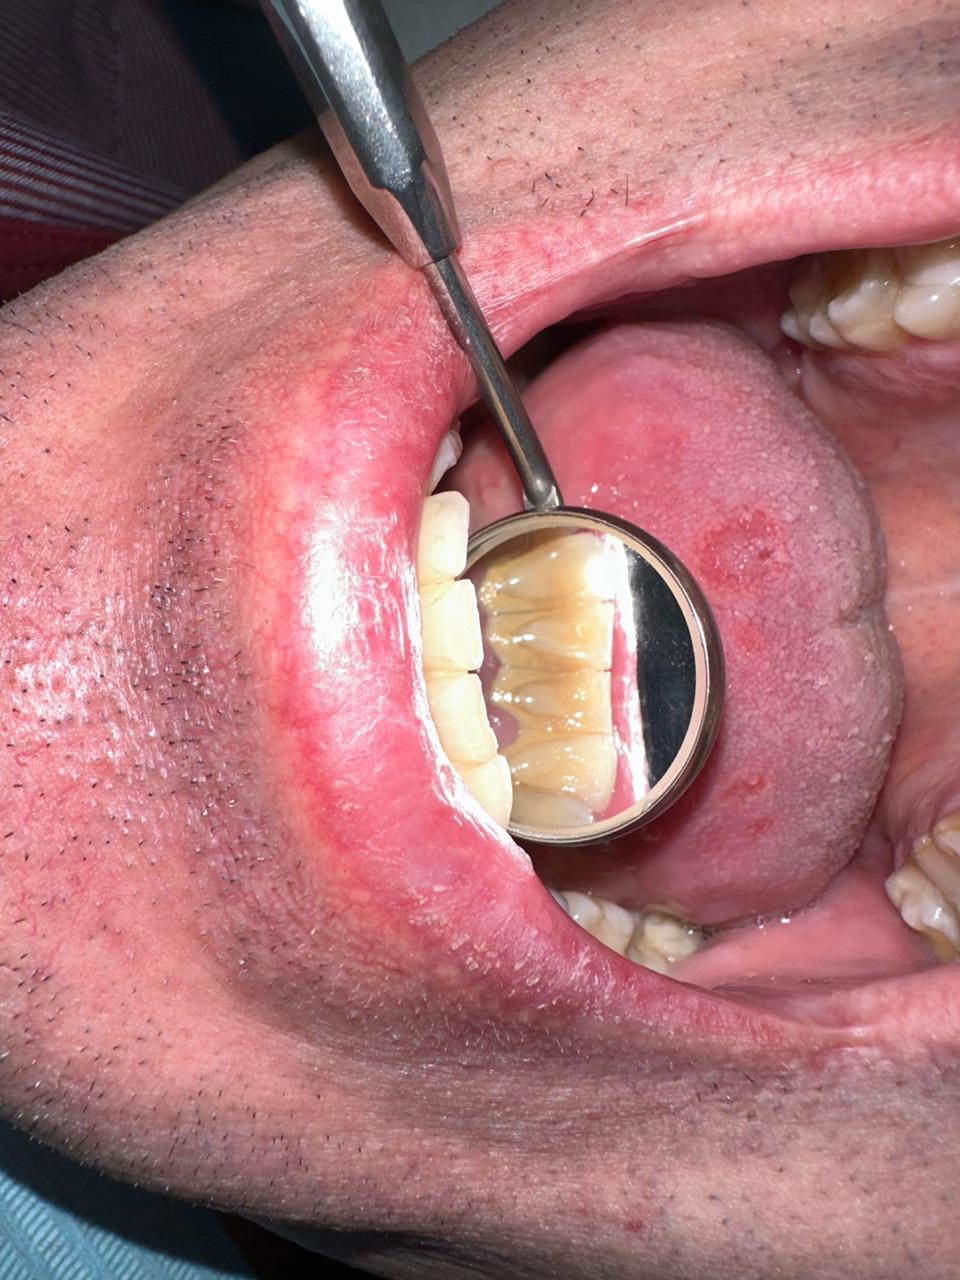

Снятие зубных отложений и зубного камня

Профессиональная гигиена полости рта играет важную роль в поддержании общего здоровья полости рта и предотвращении развития различных заболеваний!

Пескоструйная обработка - полирует поверхности зубов и убирает зубной камень в труднодоступных местах, а так же обладает выразительным отбеливающим эффектом, на 1-2 тона. Процедура абсолютно безболезненна, не травматична, эффективна.